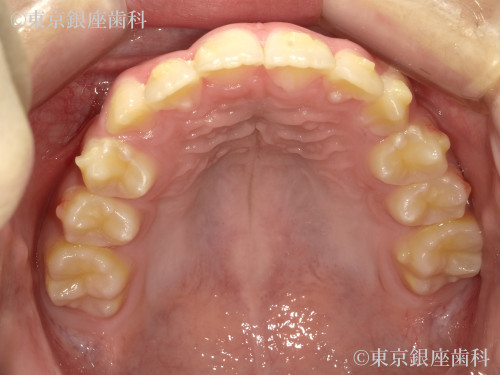

Before

インビザライン:ファースト